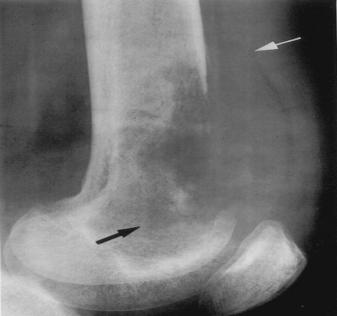

好发部位:股骨头、胫骨结节、椎体骺板、腕舟月骨、足舟骨等。

股骨头骨骺缺血性坏死:骨骺变小、碎裂变形,颈短粗,头向外移,内侧间隙增宽。

成人股骨头缺血性坏死:股骨头变形,增骨质生硬化囊变并存;左侧间隙变窄,右侧间隙正常。关节间隙变窄,退行性骨关节病,股骨头呈磨菇头状变形